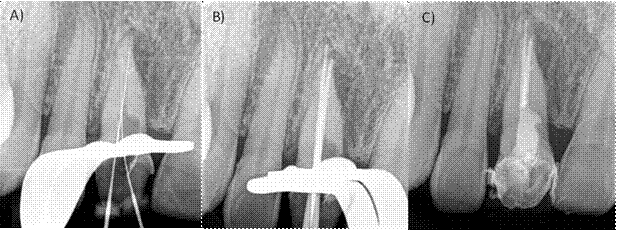

A la exploración clínica observamos una tumefacción de los tejidos en la zona anterosuperior y presencia de tracto sinusal, una restauración desajustada correspondiente a una corona libre de metal, invasión del espesor biológico, inflamación gingival, dolor a la masticación, percusión horizontal y vertical (Fig. 1B). En la radiografía periapical del órgano dental #11 (orto-radial y mesio- radial) observamos lesión radiolúcida en la raíz a nivel apical y mesial, perdida de la cresta ósea interproximal y lamina dura no visible. En la porción apical observamos una subobturación (Fig. A,C). Se realizó una TCHC y al observar la tomografía se confirmó la presencia de dos raíces en dicho órgano dentario de las cuales, solo la raíz vestibular estaba tratada endodónticamente (Fig. 2 A-B). Diagnóstico: Órgano dental previamente tratado con absceso apical crónico29. Se anestesio con articaína 4% con epinefrina 1:100 000 supraperióstica en fondo de saco anestesiando el nervio alveolar anterior, se eliminó la restauración coronaria utilizando una fresa de diamante y pieza de mano de alta velocidad, una vez retirada, se realizó aislamiento absoluto con dique de goma, se procedió a eliminar la gutapercha con limas Wave One Gold (Dentsply Sirona, Tulsa Dental), se exploró el conducto palatino con limas tipo K 6 y 8 hasta lograr permeabilizarlo, la longitud de trabajo de ambas raíces se obtuvo con la ayuda de localizador apical Apex ID (SybronEndo, Orange, CA)(Fig.3A), se instrumentó con limas Wave One Gold (Dentsply Sirona, Ballaigues, Switzerland ) Large (45/05) para el conducto vestibular y médium (35/06) para el conducto palatino, la irrigación se realizó con hipoclorito al 5.25 % durante todo el tratamiento para finalizar con un protocolo de irrigación de 3 ciclos de 20 segundos, hipoclorito de sodio 5.25%, agua destilada y EDTA 17% (Smear clear Sybron Endo, CA), activados con ultrasonido (Ultra X, Eighteeth Medical), se colocó hidróxido de calcio como medicación intraconducto durante 15 días. La segunda cita se realizó nuevamente protocolo de irrigación, los conductos se secaron con puntas de papel estériles y fueron obturados con técnica de onda continua de calor (Fast fill and Fast Pack, Eighteeth Medical) y cemento AH-Plus (Dentsply Maillefer, Ballaigues, Switzerland) (Fig. 3 B-C), por último, se utilizó resina fluida para el sellado del acceso coronal. Se solicitó una segunda TCHC para evaluar la correcta localización y obturación del órgano dental (Fig. 4 A-B).

Figura 3: A) Radiografía intraoperatoria donde se observa el conducto completamente desobturado y la determinación de la longitud de trabajo. B) Prueba de punta principal C) Radiografía postoperatoria inmediata.